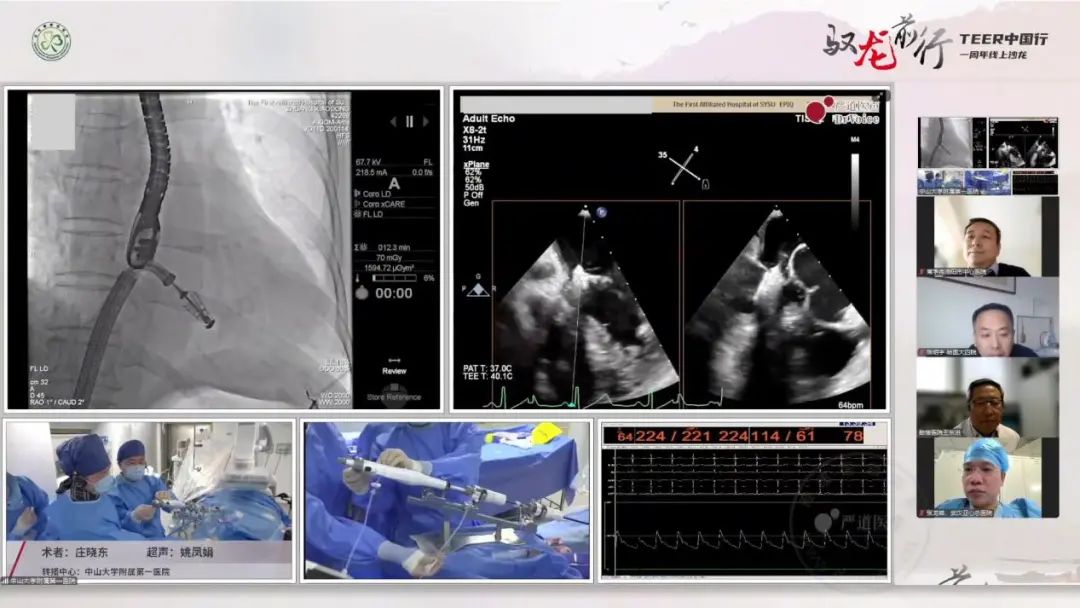

中山大学附属第一医院庄晓东教授团队倾力呈现一场精彩娴熟的TEER手术直播,南京大学医学院附属鼓楼医院王东进教授、武汉亚心总医院张龙岩教授担任主持;洛阳市中心医院常学伟教授、云南省第一人民医院庞明杰教授、南通大学附属医院盛红专教授、哈尔滨医科大学附属第四医院张明宇教授出席特邀讨论嘉宾。患者二尖瓣广泛脱垂,P3区累及P2区,且脱垂高度较高,房间隔较短,同时主动脉窦增宽,后叶存在钙化,具有较大挑战。庄晓东教授与在线嘉宾就穿刺高度不足、术中主动脉窦遮挡等操作技巧进行热烈交流,最终一枚长宽+一枚长窄夹,将脱垂完全消除,反流降至微量以下。